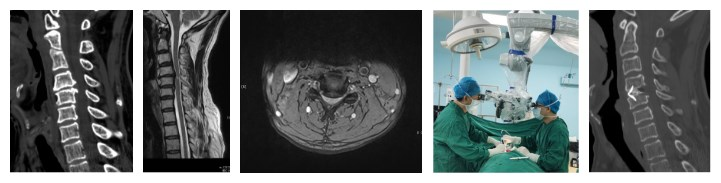

擴(kuò)張通道/雙通道內(nèi)鏡下腰椎減壓、融合內(nèi)固定術(shù)+經(jīng)皮椎弓根螺釘內(nèi)固定術(shù)主要適用于1-2個(gè)節(jié)段中老年腰椎退變嚴(yán)重的椎管狹窄患者,手術(shù)時(shí)間2-3小時(shí),出血50-300ml,手術(shù)切口2-4個(gè),每個(gè)長(zhǎng)度約1.5cm-4cm,采用肌間隙入路,創(chuàng)傷小,術(shù)后1-2天下地活動(dòng),術(shù)后4-7天可出院。

例:65歲女性患者,診斷為“L4/5椎間盤突出癥”,行雙通道內(nèi)鏡下腰椎減壓、融合內(nèi)固定術(shù)+經(jīng)皮椎弓根螺釘內(nèi)固定術(shù)。